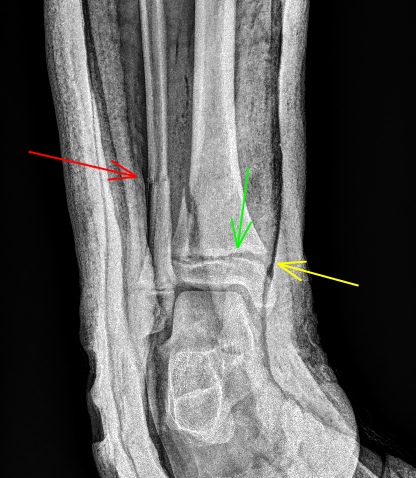

3/10/2025.🦴⚠️69yo male, h/o bilateral TKA, c/o R knee pain. XR (Right knee): 🟥 Loss of polyethylene + metal-on-metal contact 🟨 Prosthesis loosening 🟩 Capsular distension w/ metallic debris ✅ Left knee: normal ❌ Right knee: advanced metallosis #Metallosis #Radiology #TKA